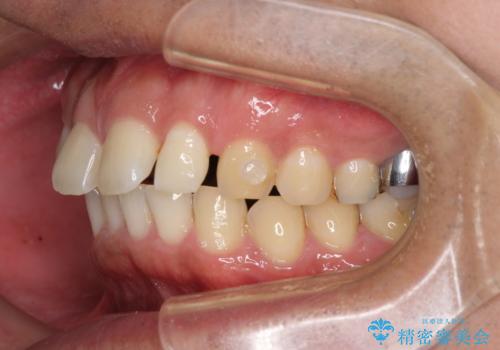

- 上顎前歯の突出感とすきっ歯を気にして来院された患者様です。

奥歯の咬み合わせを見ると、下顎に対して上顎が前方に位置していたため、補助装置により上顎歯列全体を後方に移動させ、その後インビザラインにて歯列全体を整えることとしました。